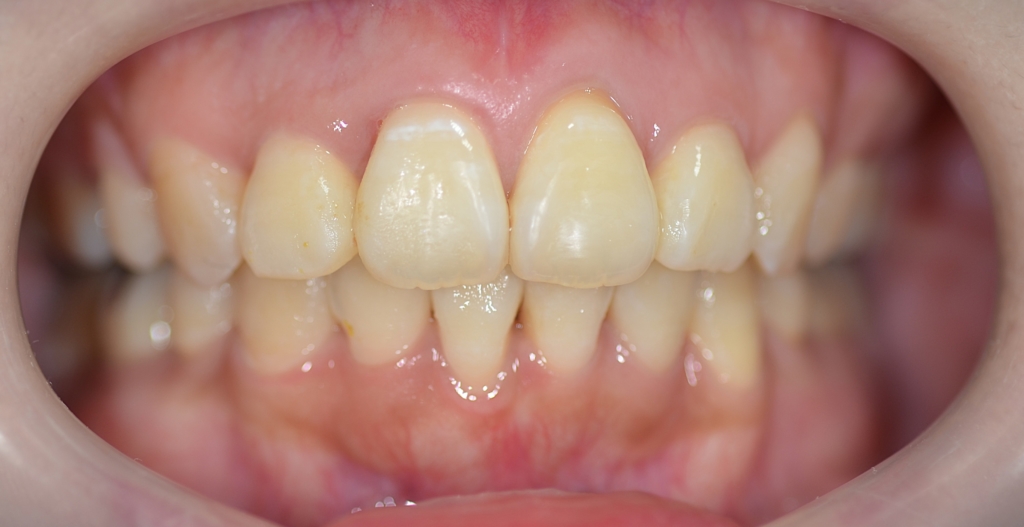

【After】

上下の正中がちょっとズレてしまいました。

患者さん的には「コレくらいなら何の問題もありません!」と温かい言葉をいただき許してもらいました。

歯並びはキレイになり、大きくズレていた上下の歯並びの正中(真ん中)大体一致しました。

最終時点で、「上の前歯に出来た「ブラックトライアングル」が気になる」との訴えがありました。

そこで、前歯の間をストリッピングという処置を行い、若干歯を小さくして、その分だけ前歯を絞り込みブラックトライアングルを解消する!という仕上げ処置を行いました。

*元の歯並びの凸凹がひどい場合には、このブラックトライアングルが生じやすくなります。

限界はありますが、ある程度の解消は可能です。